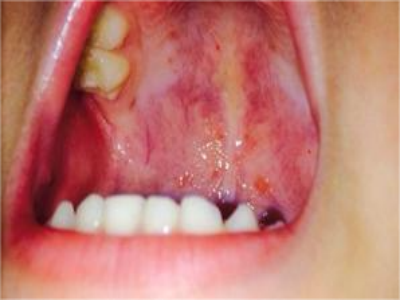

小儿口疮咽喉黏膜有零散的白点状溃疡图

小儿口疮表现为靠近咽喉处的黏膜上出现零散的白色小溃疡,主要表现为奶白色的斑点,周围红肿,伴有发热、咽喉肿痛等症状,需要遵医嘱应用药物治疗。